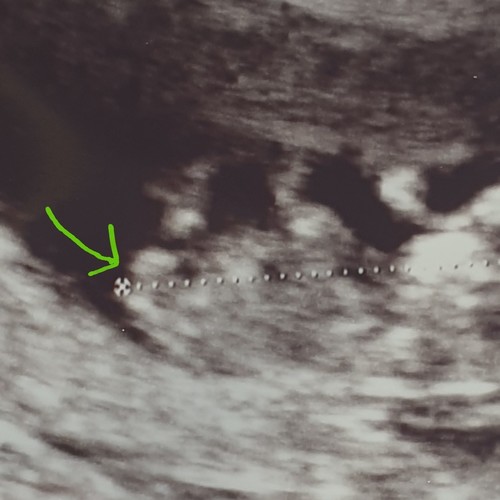

Is dat niet de navelstreng?? Althans dat zei mijn v.k. of. ?

Afgaand op de NUB theorie is mijne een meisje denk ik?

Hoeveel weken ben je op deze echo?

11+2 en de verloskundige zei dat ze het zag maar volgensmij is het echt te vroeg

Ahh oké. De nub kun je eigenlijk pas met 12 weken echt inschatten. De verlo ...

Ze zei een meisje